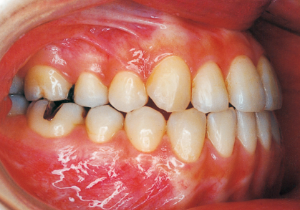

Age at Initial Visit: 8 years 1 month, Female / Protruding lower bite. Protruding lower jaw

1 Initial Visit 8-29-’79

Although there were many missing deciduous teeth, the number of permanent teeth was not problematic (4). The amount of negative overjet was significant (1). On cephalometric radiographs, the mandibular ramus was not relatively long, but the large gonial angle and the long mandibular body were noticeable, indicating an overall tendency of the mandible to project inferiorly and anteriorly. High lower facial height was also characteristic.

A potential predisposition to mandibular protrusion was clearly evident.